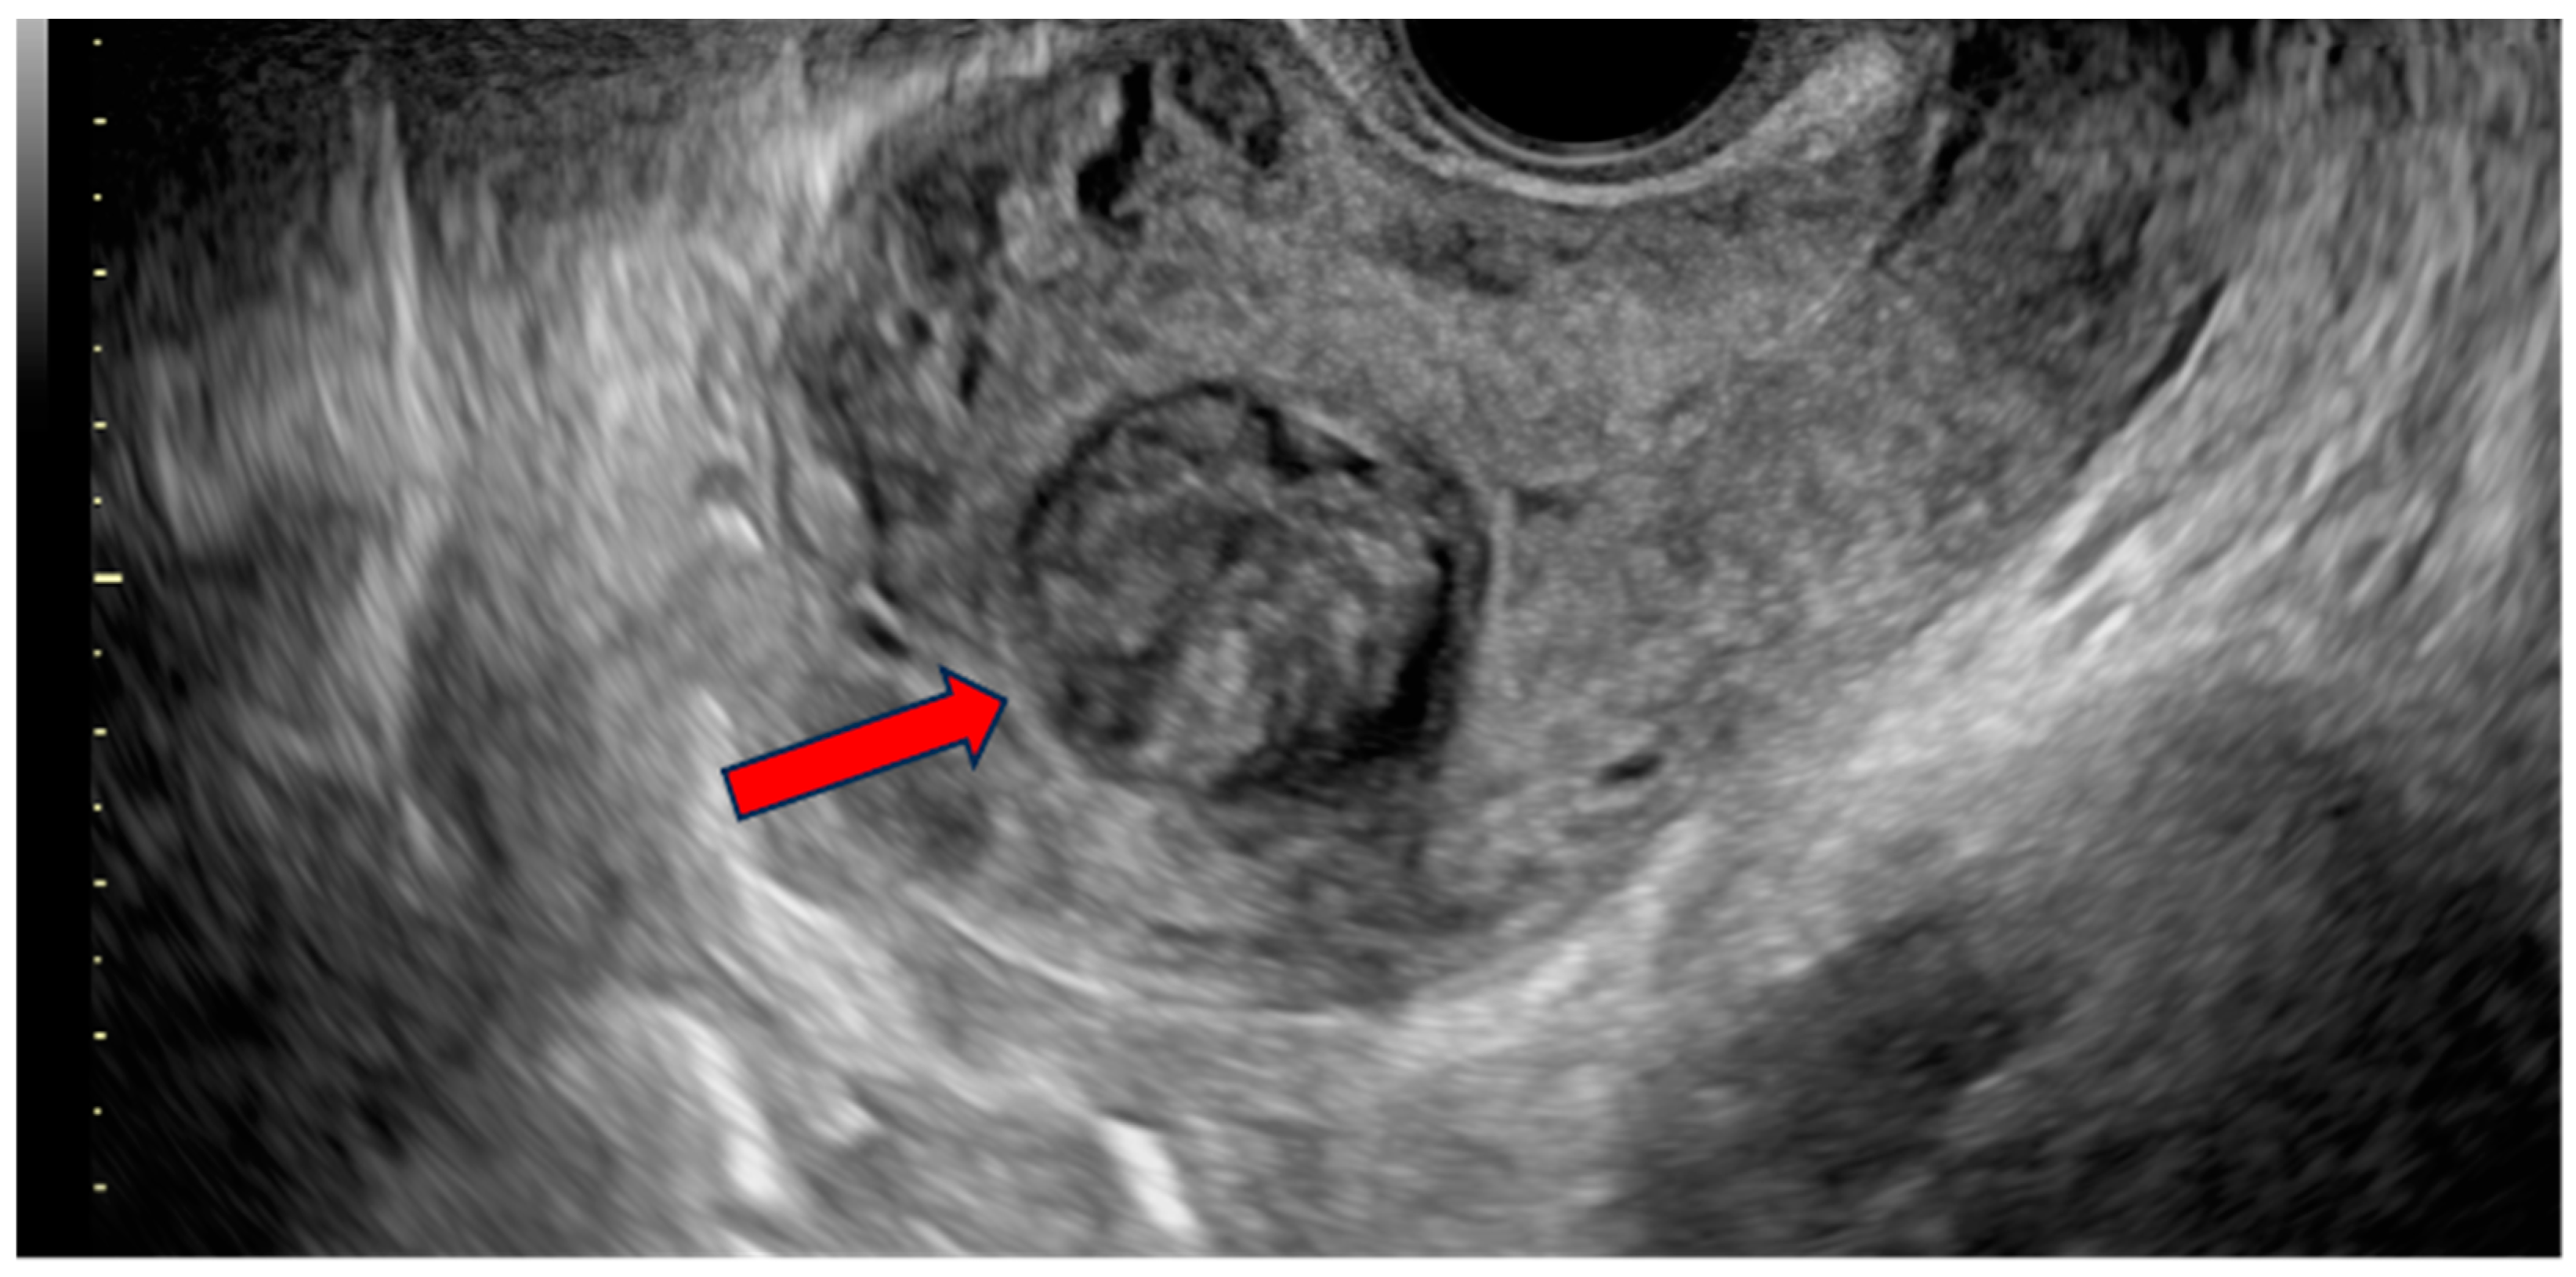

| Ultrasound features | Single oval submucosal fundal lesion; mixed echogenicity, well-defined borders without acoustic shadow. | Ultrasonographic appearance was not suggestive of malignant lesions. |